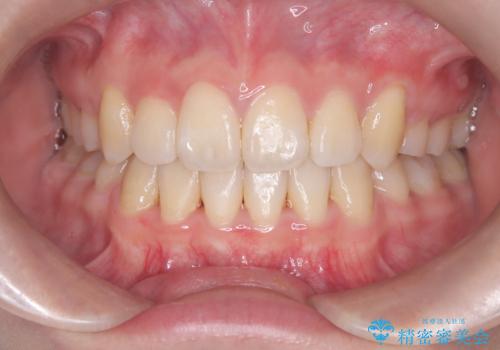

- 八重歯を主訴に来院されました。

左側犬歯が埋伏していましたが、第一小臼歯(4番目の歯)を抜歯したことでできたスペースに牽引し、右側の飛び出した八重歯を含め、歯全体を整列することができ患者様も満足していただきました。